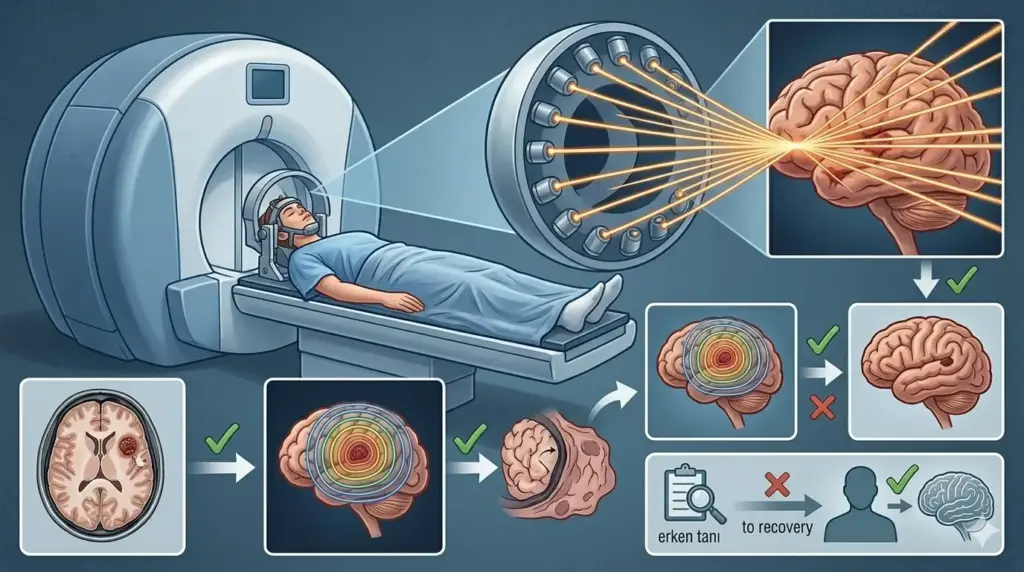

● Radyocerrahi (Gamma Knife), beynin derin ya da cerrahi açıdan ulaşılamaz bölgelerindeki kavernomlar için alternatif bir seçenektir.

Gamma Knife Radyocerrahisi: Üçüncü Seçenek

Cerrahi açıdan ulaşılamaz kavernomlar ya da genel sağlık durumu nedeniyle açık ameliyata uygun olmayan hastalarda Gamma Knife stereotaktik radyocerrahisi değerlendirilebilir. Bu yöntemde yüksek dozda odaklanmış radyasyon, lezyona verilerek damarsal yapıda fibrozis (sertleşme) sağlanır ve kanama riski azaltılmaya çalışılır.

250’den fazla hastayı kapsayan bir çalışmada, nöbet tablosu olan hastalarda Gamma Knife sonrası yüzde 82’sinde nöbet kontrolünde iyileşme gözlemlenmiştir (Gamma Knife İstanbul, 2025). Bununla birlikte, Gamma Knife’ın kavernomun fiziksel varlığını ortadan kaldırmadığı ve etkisinin tam olarak ortaya çıkması için 2–3 yıllık bir süre gerektirdiği akılda tutulmalıdır.

Tanıdan İyileşmeye: Süreç Nasıl İlerliyor?

Kavernom nöbeti şüphesiyle başvuran bir hasta için süreç genellikle aşağıdaki aşamaları izler:

- İlk muayene ve anamnez: Nöroloji uzmanı, nöbet türünü (fokal mi, jeneralize mi?), başlangıç yaşını, nöbet sıklığını ve aile öyküsünü ayrıntılı biçimde sorgular. Kullanılan ilaçlar, dozlar ve yanıt değerlendirilir.

- Görüntüleme: Tanının temel aracı MRG’dir. Özellikle T2 ağırlıklı sekanslar ve SWI (duyarlılık ağırlıklı görüntüleme) hemosiderin halkasını ve “patlama mısırı” görünümünü net olarak ortaya koyar. Konvansiyonel anjiyografi kavernomda tanıya katkı sağlamaz; gerekli değildir.

- EEG: Nöbet kaynağının lokalizasyonunu ve epileptojenik odağın haritasını çıkarmak için elektroensefalografi çekilir.

- Multidisipliner değerlendirme: Nöroloji, nöroşirurji ve gerektiğinde nöroanestezi uzmanlarının bir arada karar verdiği bu süreçte; konuma ve tabloya göre fonksiyonel beyin cerrahisi seçenekleri de değerlendirme kapsamına alınır.

- Cerrahi (mikrocerrahi rezeksiyon): Genel anestezi altında, kraniyotomi yöntemiyle kavernom çıkarılır. Ameliyat süresi ortalama 1–3 saattir; modern nöronavigasyon ve intraoperatif MRG sistemleri, önemli beyin yapılarına zarar verilmeden tam çıkarım yapılmasına olanak tanır.

- Hastanede kalış süresi: Komplikasyonsuz vakalarda hasta genellikle 3–5 gün içinde taburcu edilir.

- İyileşme ve takip: İşe dönüş çoğunlukla 2–4 hafta içinde mümkün hale gelir; ağır fiziksel aktivite ve sürüş için 4–6 haftalık kısıtlama önerilir. Ameliyat sonrası nöbet durumuna bağlı olarak antiepileptik ilaç kullanımı sürdürülebilir ya da zamanla azaltılabilir. İlk yıl 3–6 ayda bir, sonrasında yıllık MRG takibi planlanır.

Prof. Dr. Erdinç Özek, klinik pratiğinde ameliyat öncesi nöbet süresinin kısa tutulmasının — özellikle 1 yılın altında — postoperatif nöbet kontrolünü belirgin biçimde iyileştirdiğini vurguluyor; bu da erken değerlendirmenin neden önemli olduğunu açıkça ortaya koymaktadır.